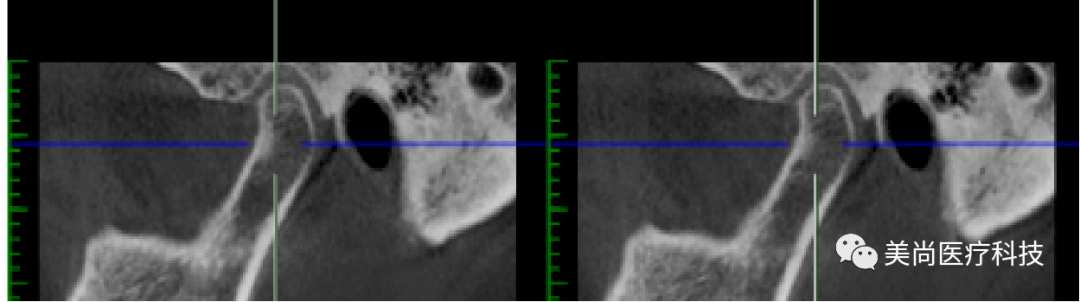

32、42可用骨宽度6mm,可用骨高度10mm;

34、44可用骨宽度6mm,可用骨高度11.5mm。

制作导板,导板引导下植入种植体

导板下植入植体:

在32、42处植入3.5*10mm植体各一颗,植入扭矩约35n.cm;

在34、44处植入4.0*11.5mm植体各一颗,植入扭矩约40n.cm。